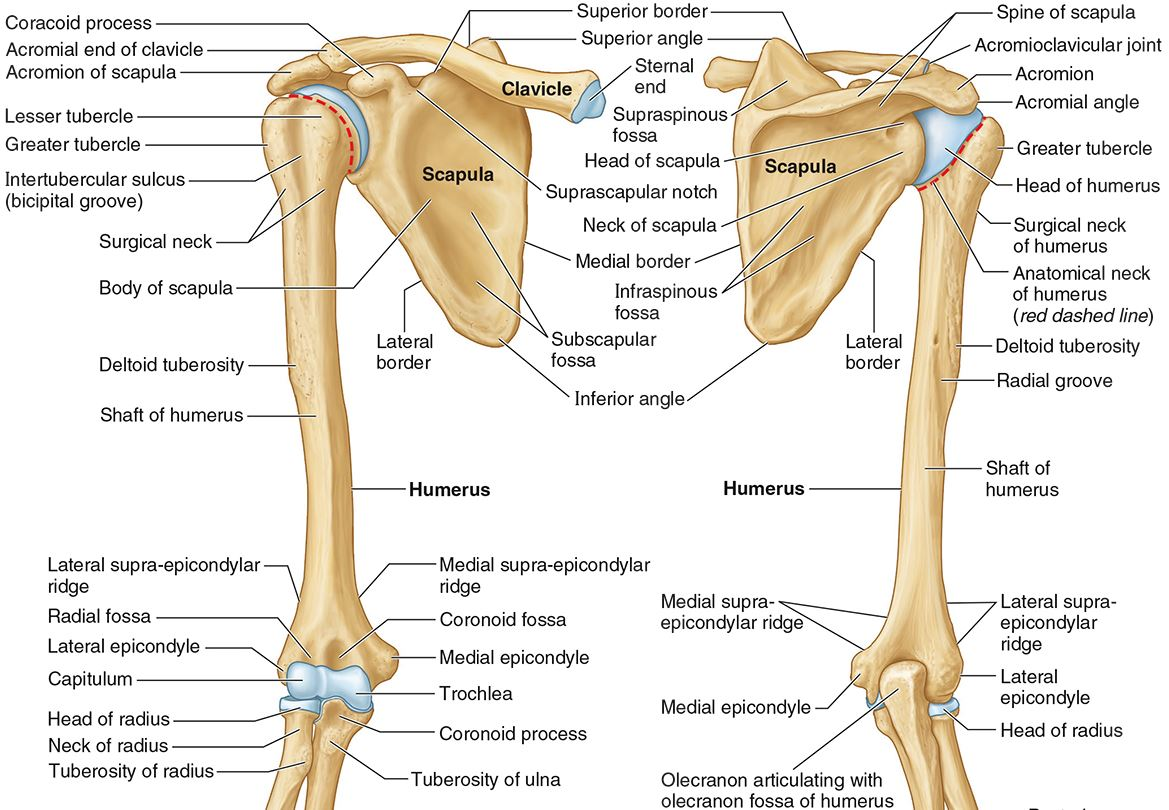

What part of the humerus is this?

The head of the humerus articulates with the scapula at the glenohumeral joint.

What part of the humerus is this?

The anatomic neck is an indentation distal to the head and provides an attachment for the fibrous joint capsule of the glenohumeral joint.

What part of the humerus is this?

The greater tubercle lies lateral and distal to the anatomic neck.

What part of the humerus is this?

The lesser tubercle lies on the anterior/medial side of the humerus, just distal the anatomic neck.

What part of the humerus is this?

The intertubercular (bicipital) groove lies between the greater and lesser tubercles.

What part of the humerus is this?

The surgical neck is a narrow area distal to the tubercles. It is a common site for proximal humerus fractures.

What part of the humerus is this?

The humeral shaft features the deltoid tuberosity laterally for the distal insertion of the deltoid muscle.

What part of the humerus is this?

The radial groove is an oblique depression that contains the radial nerve and deep brachial artery.

Which parts of the humerus is this?

The medial and lateral epicondyles are distal prominences to which many forearm tendons attach, near the elbow joint.

Which parts of the humerus is this?

The medial and lateral supracondylar ridges extend superiorly from the medial and lateral epicondyles.

Which parts of the humerus is this?

The trochlea and the capitulum (the condyles) are the most distal surfaces of the humerus, where it articulates with the forearm bones at the elbow joint

What part of the humerus is this?

The olecranon fossa is a posterior depression above the trochlea that receives that olecranon process of the ulna

What part of the humerus is this?

The coronoid fossa is an anterior depression above the trochlea that receives that coronoid process of the ulna.